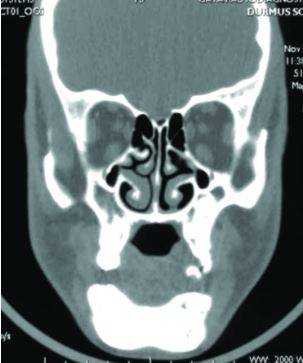

Особенности строения верхнечелюстной пазухи на КТ

По форме гайморовы пазухи напоминают усеченную четырехгранную пирамиду. В среднем, объем каждой полости составляет 10-13 см³. Размеры не являются постоянными и меняются с развитием лицевого скелета. У здорового человека толщина слизистой оболочки верхнечелюстных синусов примерно 1,0-1,5 мм. При воспалительных процессах, аллергии, простудных заболеваниях ткани отекают и гипертрофируются, что способствует утолщению стенок и уменьшению объема полостей. Патология хорошо просматривается на изображениях КТ верхней челюсти и гайморовых пазух.

Левая и правая костные каверны , как правило, симметричны. Но у некоторых пациентов при обследовании выявляют аномалии, такие, как разделение полости перегородками на несколько камер. Такое строение синуса создает определенные трудности в лечении гайморитов.

КТ верхней челюсти ценно не только в отношении изучения строения гайморовых пазух. Диагностика на компьютерном томографе дает возможность детально исследовать структуру альвеолярного отростка (зоны верхнечелюстной кости, где расположены зубы) и анатомо-топографическое соотношение корней зубов с дном полостей пазух.